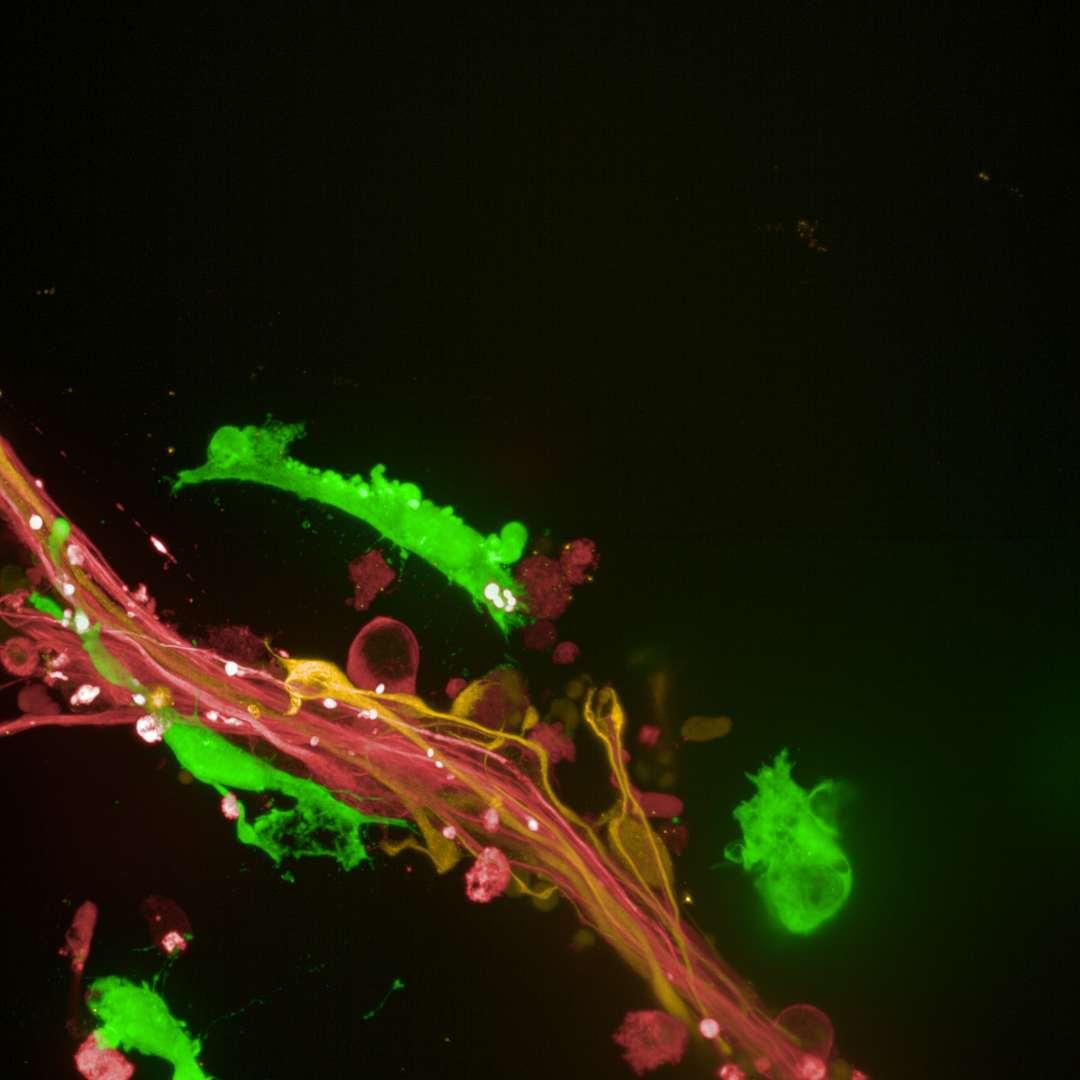

• Isogenic control or SNCA A53T mutation neurons were plated in both chambers of a microfluidics device then cultured to allow the neurons to connect via the microchannels

• PFFs were added to the donor chamber only before fixing and labelling for pS129 α-synuclein

• pS129 positive neurons were detected in donor chambers due to directly applied PFFs and acceptor chambers due to seeded PFFs, though automated analysis failed to detect the small proportion of positive wildtype neurons in acceptor chambers

Projection of neurites through microchannels at 2 weeks

• A53T mutation increases pS129 pathology in both donor and acceptor chambers